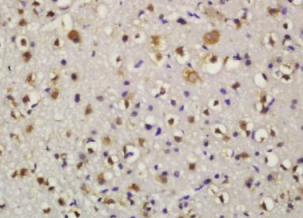

组织/细胞:小鼠脑组织;4%多聚甲醛固定石蜡包埋;

抗原提取:柠檬酸缓冲液(0.01M,pH 6),15min煮沸,用3%过氧化氢阻断内源性过氧化物酶30min;37℃下阻断缓冲液(正常山羊血清)20 min;

孵育:抗BID多克隆抗体,未结合1:200,在4°C下过夜,然后与二级抗体结合,DAB染色。